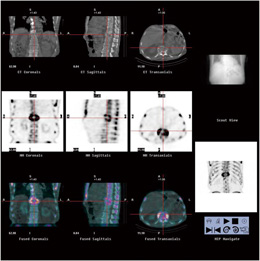

SPECT検査とは SPECTとは、single photon emission computed tomography(単一光子放射型コンピュータ断層撮影)の略です。 ラジオアイソトープという放射性物質を含む薬剤(放射性医薬品)を体内に投与し、薬剤から放出される放射線を特殊なカメラで検出して、臓器の状態を画像化する検査です。 体内に入った薬剤は、特定の臓器に集まり、そこから放射線を出します。 この. SPECT (スペクト)は、Single Photon Emission CT (シングル・フォト・エミッションCT)の略で、単一光子放射型コンピュータ断層撮影ともいいます。 原理は基本的に PET (ペット)検査 と同様で、微量の放射線を出す放射線医薬品を体内に注入し、放出される放射線を特殊なカメラで撮影してその分布状況を断層画面でみる検査です。 CT 、 MRI検査 ではおもに「臓器の形や大きさ. 図7 心電図同期心筋血流spect検査:左室容積ならびに駆出率の計測 脳のri検査 脳梗塞や脳血管の動脈硬化が疑われる患者さんで、脳虚血の重症度評価や脳血行再建術の適応決定・効果判定のために利用されています。.

吸収補正用x線ct搭載可能spect装置infinia 技術解説 Geヘルスケア ジャパン株式会社 Innavi Suite